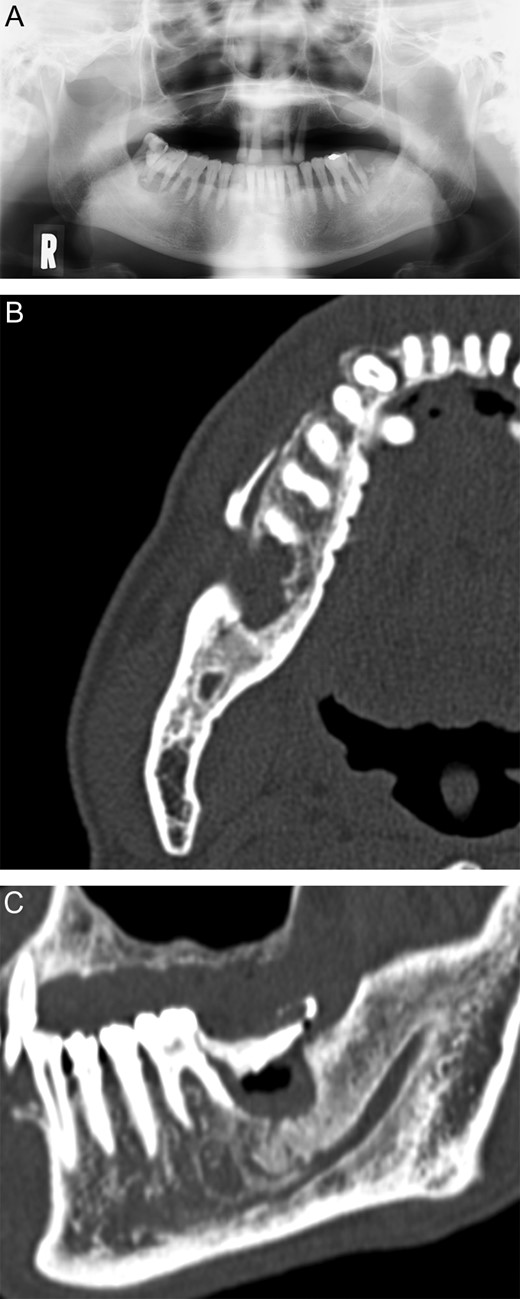

At the initial visit, his chief complaints were bleeding from the gums and difficulty opening his mouth. The right molar teeth (47 and 48) showed Grade III mobility, and their gingivae were painful with continuous bleeding. His maximum mouth opening was 18 mm (Fig. 1A). The right molar teeth (46 and 47) showed Class III alveolar ridge deficiency on panoramic radiographs and were mobile teeth (Fig. 2A). We cauterized the bleeding points with an electrosurgical knife. We packed an absorbable haemostat (Surgicel; Ethicon, Somerville, NJ, USA) into the gingivae and sutured 3–0 silk threads above it. Finally, we used surgical dressing packs (COE-PAK; G.C. America, Alsip, IL, USA).

(A) Panoramic radiograph on 12 June 2012. (B) Coronal view of the computed tomography images on 25 June 2012. (C) Sagittal view of the computed tomography images on 25 June 2012.

The Internal Medicine Department assigned a clinical diagnosis of CMMoL, based on the blood and bone marrow examinations conducted on 13 June 2012. Computed tomography on June 25 indicated that bone absorption had nearly reached the right inferior alveolar canal, and a ring of sequestrum was present under tooth 47 (Fig. 2B and C). We diagnosed right mandibular osteomyelitis, based on these clinical features.